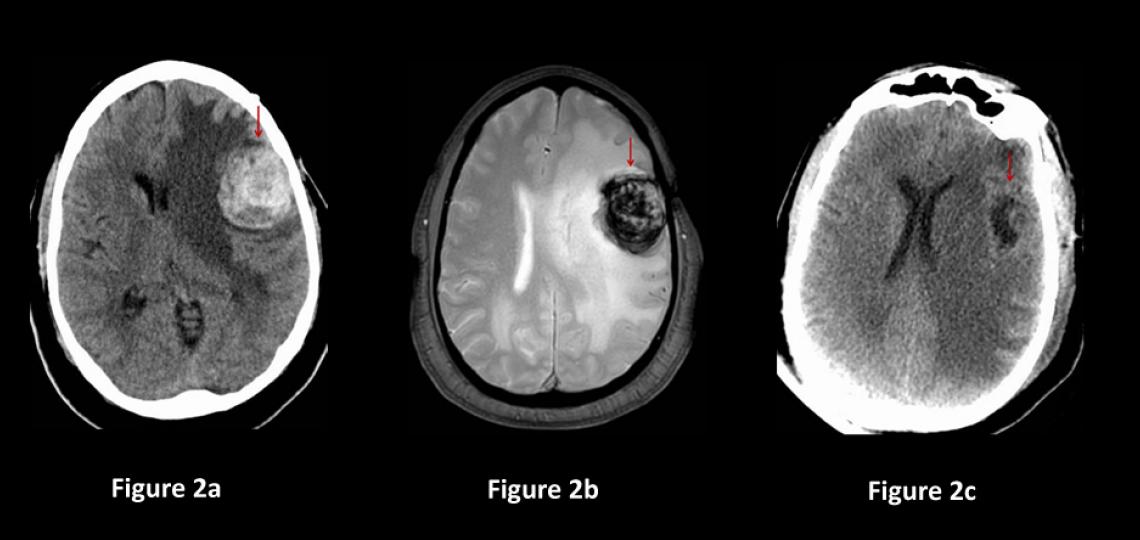

Generally, cavernous malformations that are small, not causing symptoms or located in critical brain areas are not treated immediately but rather monitored (Figure 1). Most such patients are "followed" by repeat MRI scan every year for several years, then if there is no growth, the MRIs are spaced out every two to five years after that. Treatment may be needed if the lesion grows or causes new symptoms.

Figure 1a: CT scan of the brain in a patient with a mild headache showing a small spot of white bleeding (red arrow). Figure 1b: Brain MRI scan showing a small cavernous malformation (red arrow) in the frontal lobe. Figure 1c: Brain MRI sequence showing the presence of bleeding (red arrow).